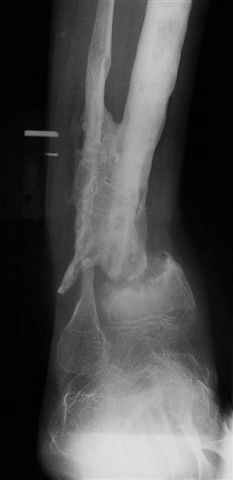

The case:Женщина 24 лет non union дистальной тибии с укорочением 7cm.

Все началось с перелома голени лет 8 тому назад. Остеомиелит - Илизаров в Kentucky, USA (деталей нет) и полтора года тому назад перелом средней трети тибии (1). Наложен унилатеральний фиксатор. Перелом зажил, но образовался стержневой остеомиелит дистального стержня. Потом нон юнион. В настоящий момент нет клинических признаков инфекции. Раны зажили.(2) Нон юнион подвижный и есть незначительное движение в голеностопе. Укорочение 7см. (3) Хотел бы знать мнение участников Форума. Благодарю. Nikolaj Wolfson,West Virginia, USA

LNS> юнион подвижный и есть незначительное движение в голеностопе. Укорочение

LNS> 7см. (3)

По представленным снимкам мне не удалось понять форму и рзмеры отломков. по-моему, нет чистой боковой проекции. Интересно бы поглядеть на более информативные снимки.